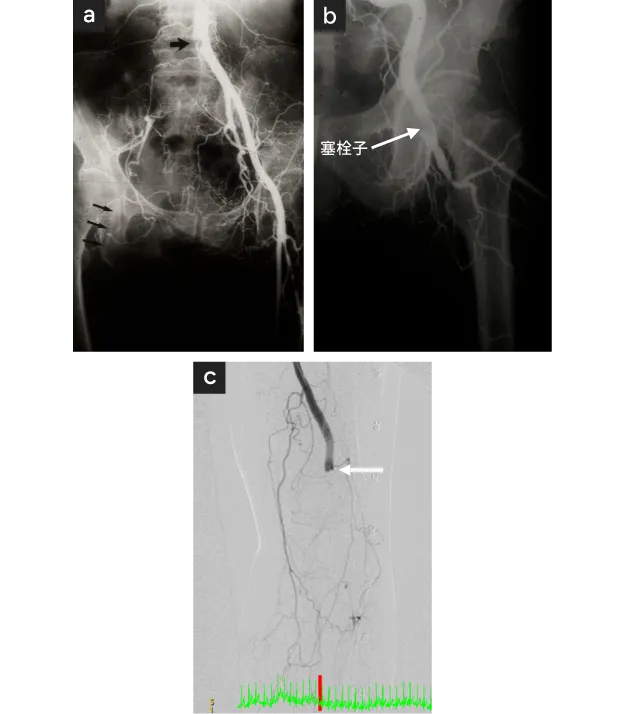

30〜40才代のアジア人の主に男性で、たばこを20本/日以上を吸い、指や趾(足のゆび)の冷感、疼痛、潰瘍、壊疽などが出現した場合〈図1 a,b,c〉、“ふくらはぎ”や足の裏の間欠性跛行がある場合などはバージャー氏病(Buerger's disease, TAO, 閉塞性血栓血管炎)が疑われます。

血行障害の検査と最終的には動脈造影検査が必須です。動脈造影ではバージャー氏病に特徴的ないくつかの所見(途絶閉塞、木の根型閉塞 treeroot、橋渡し血行路 bridging、コルク栓抜き状血行路 corkscrewなど)が認められます〈図2〉。また遊走性静脈炎という腕や足の皮下静脈の炎症も特徴的で、治癒後は血管に沿って黒く色素沈着を残します。